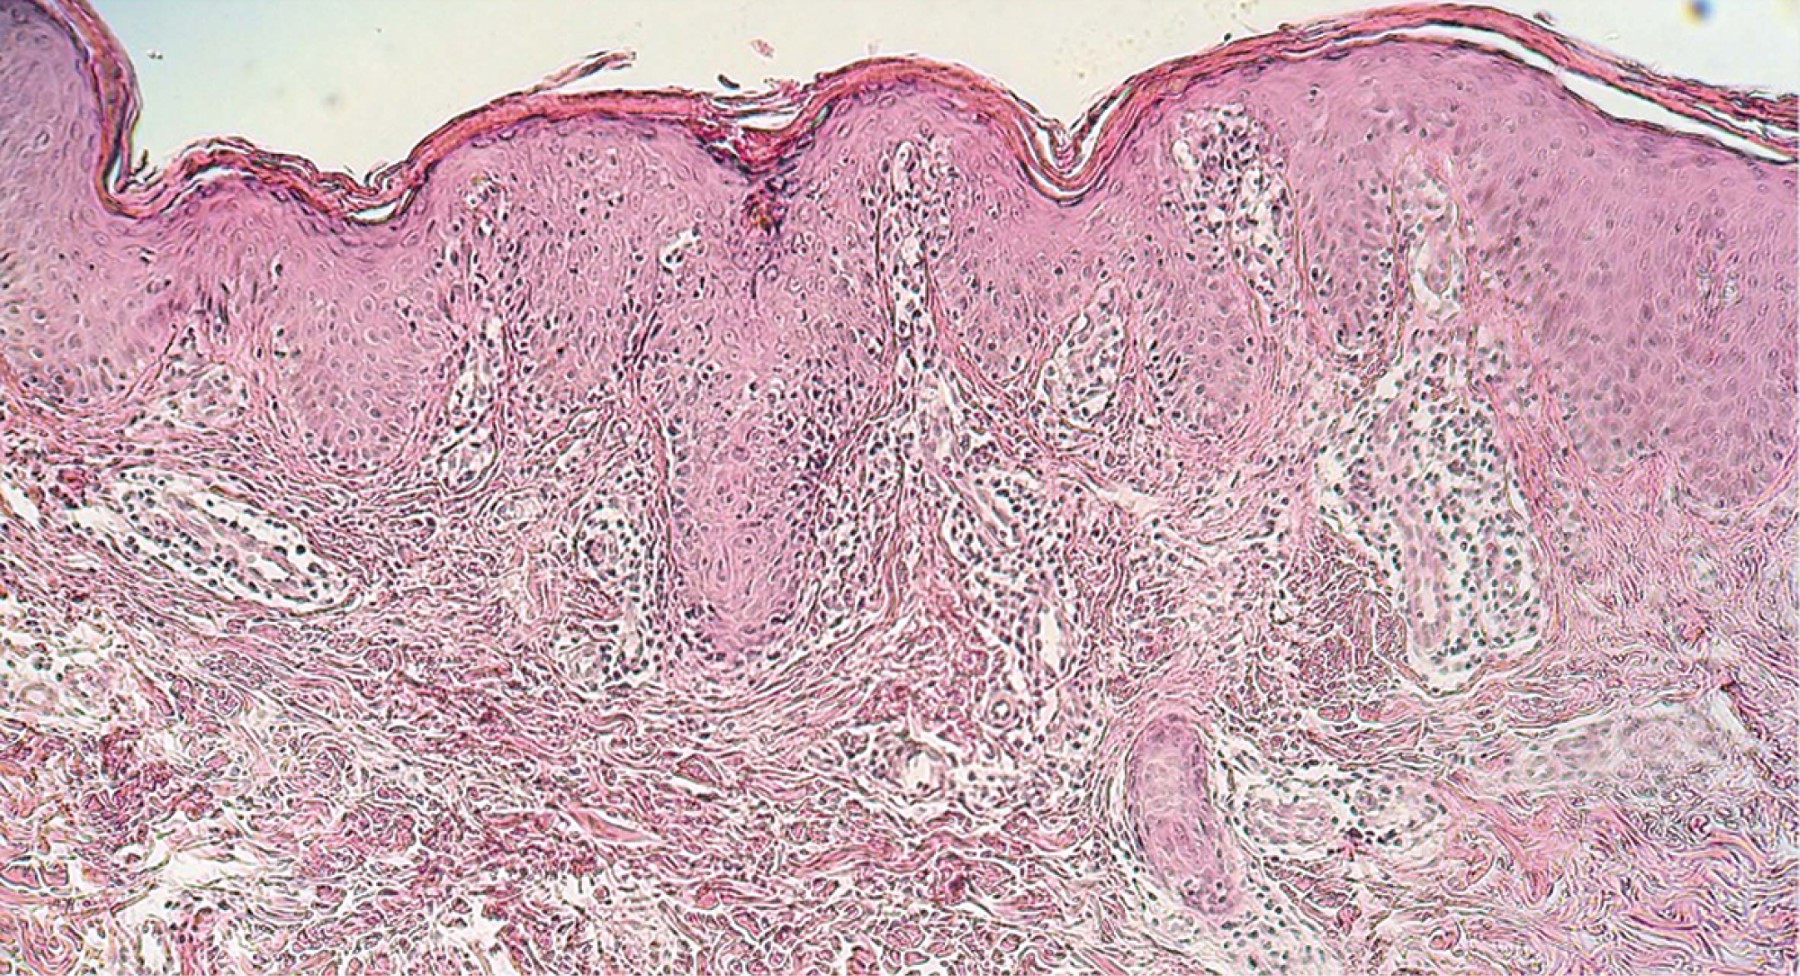

Mycosis fungoides, papular variety

Mycosis Fungoides, papular variety, cutaneous T-cell lymphoma.

Mycosis fungoides is the most common manifestation of T-cell lymphoma at the cutaneous level. At present there are different clinical-pathological varieties. Papular variant was recently described. Its evolution and prognosis vary depending on the time of evolution, being classified as papular mycosis fungoides of "early onset, or late onset". In this article we report the case of a 21-year-old female patient who came to a consultation due to presenting early-onset papular neoformations, diagnosed as papular micosis fungoides, who evolved favorably with the prescribed treatment.

Figure 2